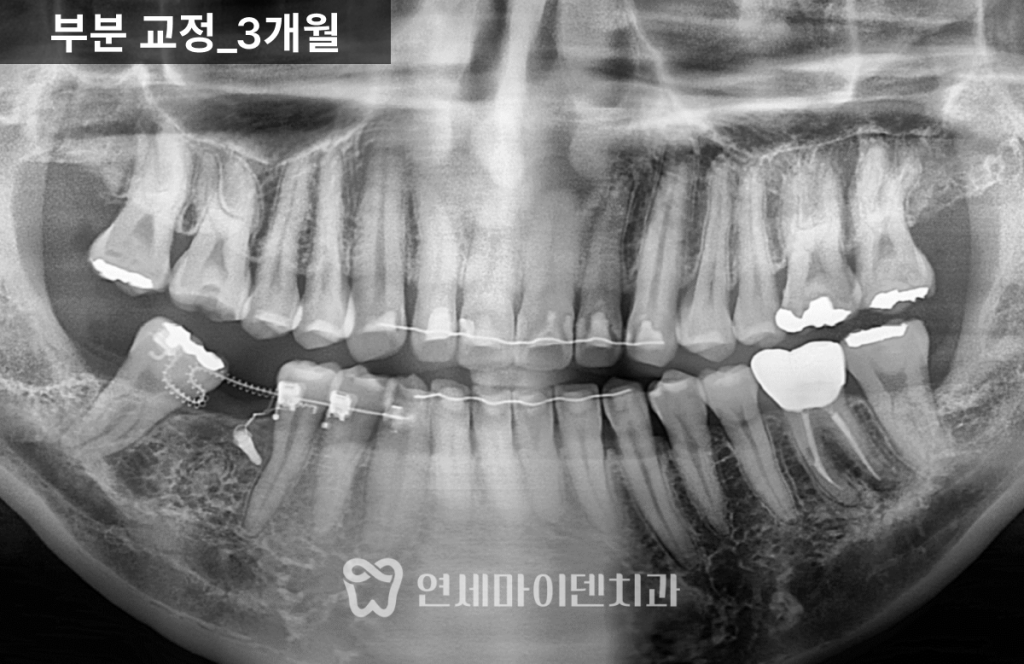

초기에는 얇고 유연한 와이어로 배열을 잡고

이후 코일 스프링과 접은 형태의 와이어를 적용해

치아를 세우는 힘을 단계적으로 조절했습니다.치아를 세우는 과정은

단순히 “밀어 올리는 것”이 아니라

뿌리 방향까지 함께 바로잡는 과정이기 때문에

정밀한 힘 조절이 필요합니다.치아교정 7개월차: 공간 확보

약 7개월이 지나면서

쓰러졌던 7번 치아는 눈에 띄게 세워졌고

임플란트가 들어갈 수 있는 공간이

충분히 확보되었습니다.물론 더 이상적인 위치까지

완벽하게 이동시키는 것도 가능했지만,치아 뿌리 이동 범위와

치료 기간을 고려해

교합에 무리가 없는 선에서

효율적으로 마무리하는 전략을 선택했습니다.